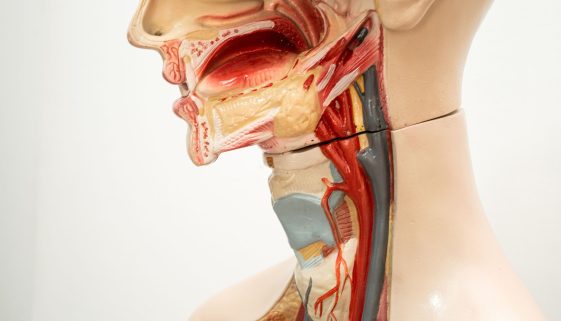

تعد الجراحة العامة للأطفال من المجالات الطبية الحساسة التي تتطلب اهتمامًا خاصًا وعناية فائقة لضمان صحة الأطفال ورفاهيتهم. يتطلب هذا النوع من الجراحة التعامل مع الأطفال بطريقة تراعي احتياجاتهم النفسية والجسدية. الهدف من هذه المقالة هو تقديم نصائح وتعليمات تثقيفية للآباء والأمهات ومقدمي الرعاية للإعداد للجراحة وضمان الشفاء السريع لأطفالهم. […]